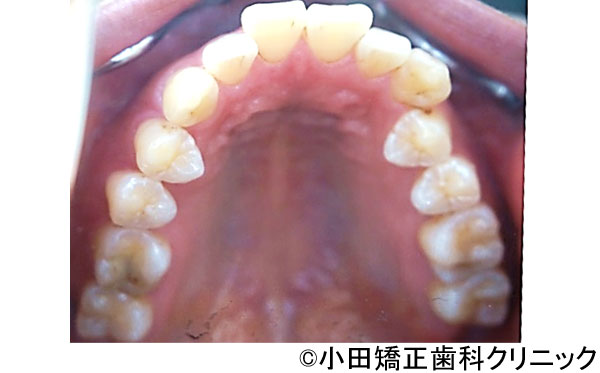

【症例3】呼吸から治して厳しいでこぼこ状態ではあるが、歯を抜くことなくしかも突出のない知的な口元に改善する治療

- 治療前

- 治療後

- 治療名

- 呼吸から治して厳しいでこぼこ状態ではあるが、歯を抜くことなくしかも突出のない知的な口元に改善する治療

- 患者様

- 9歳

- 費用

- 1,000,000円(税込)(永久歯治療を含む)

- 期間

- 早期治療2年+永久歯治療1年

治療内容

-

患者様の症状

厳しい上下歯列のでこぼこ不十分な鼻呼吸のため口呼吸が必要となり、舌、唇などの筋肉の良くない動き、つまり舌が、本来、飲み込むために上あごに引っ付くのではなく、下に下がり、口が開くことで頬が締まって上歯列は狭くなります。また下に下がった下の圧力で下歯列も内側に倒れて狭い舌歯列となります。

鼻呼吸不十分による口呼吸がもたらす締まりにかけるやや突出した口元、不適切な姿勢、免疫機構の不善によりもたらされる過大な感染症のリスク -

治療法

上歯列に固定式の拡大装置により左右の上あごの接合部を拡げて鼻呼吸に改善する。舌が収まる空間を得るために下歯列にも特殊な拡大装置により歯を支える骨の付け根からしっかりと広げる。

治療結果

美しい口元、顔立ち、健康的な呼吸をもたらし、鼻呼吸を導く徹底した従来より効果の大きい広げる装置により、厳しいでこぼこ状態を歯を抜くことなく、しかも突出の全くないきれいな口元に改善しました。